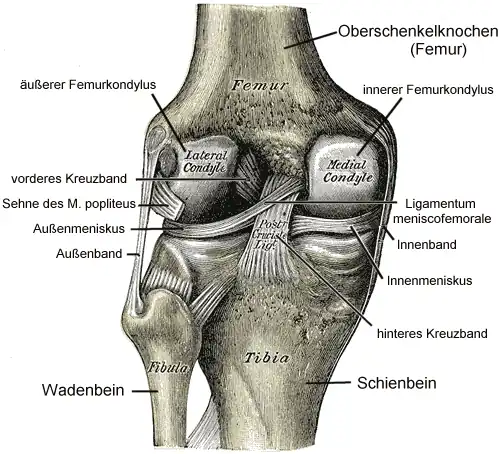

Das Kniegelenk (lateinisch Articulatio genus) ist das im Knie (lateinisch Genu, altgriechisch γόνυ gony) befindliche größte Gelenk der Säugetiere. Der Oberschenkelknochen (Femur), das Schienbein (Tibia) und die Kniescheibe (Patella) bilden dabei die knöchernen Gelenkkörper.

Das Kniegelenk ist ein zusammengesetztes Gelenk. Es besteht aus zwei Einzelgelenken, dem Kniescheibengelenk (Articulatio femoropatellaris), welches sich zwischen Oberschenkelknochen und Kniescheibe befindet, und dem Kniekehlgelenk (Articulatio femorotibialis), das zwischen Oberschenkelknochen und Schienbeinkopf (Caput tibiae) liegt. Anatomisch gesehen handelt es sich bei dem proximalen Gelenk zwischen Schienbein (Tibia) und Wadenbein (Fibula) (Articulatio tibiofibularis) zwar um ein eigenständiges Gelenk, das aber in der Regel über eine Ausbuchtung der Kniegelenkkapsel (Recessus subpopliteus) mit dem Kniegelenk verbunden ist.

Bänder

Da das Knie durch seine knöcherne Konstruktion sehr instabil ist, wird es durch zahlreiche Bänder gesichert. Sie verstärken damit die Gelenkkapsel, in deren äußere Schicht sie in der Regel eingebaut sind. Die Bänder des Knies werden nach ihrer Lage in vordere (ventrale), seitliche (kollaterale), hintere (dorsale) und zentrale Bänder eingeteilt.